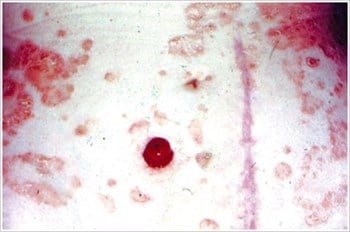

Candidiasis

Description/Causes:

Often caused by leakage, perspiration, antibiotic therapy, warm climates, broken skin.

Symptoms:

Itchy, bumpy red skin. Also, infection of vagina, armpit, mouth, or any area of skin folds (i.e., buttocks, groin).